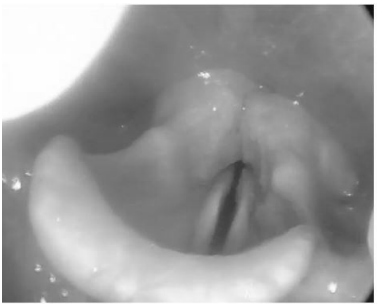

Considere o seguinte caso clínico: paciente do sexo feminino, evoluindo com dispneia leve e estridor após cirurgia de tireoidectomia total. Em videolaringoscopia realizada no primeiro dia pós-operatório, foi visualizada laringe com redução de movimentação de pregas vocais bilateralmente com redução do espaço glótico, conforme imagem. A qualidade vocal da paciente se encontrava pouco alterada. Enunciado 3175275-1

Com relação a esse caso, assinale a alternativa correta.